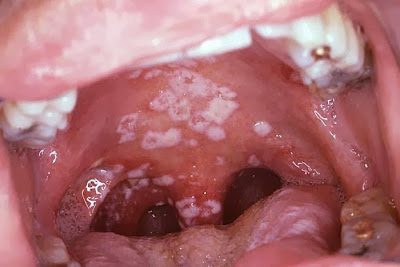

Mini, 19, mendapatkan rawatan doktor setelah mulutnya dijangkiti kudis yang teruk. Pada mulanya Mini enggan memberitahu hal sebenar tetapi apabila diasak dengan pelbagai soalan barulah remaja ini membuka rahsia.

Katanya bagi mengekalkan dara, dia sering melakukan seks oral dan seks anal dengan pasangan.

Remaja perempuan ini akan terdedah kepada penyakit kelamin seperti herpes yang menyebabkan kudis di bahagian badan.